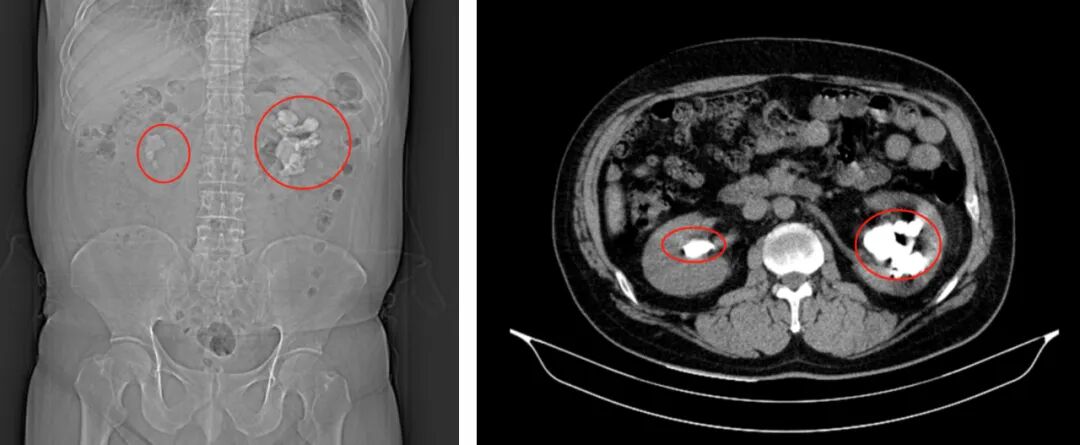

"铸型”结石占满左肾,经皮肾镜碎石取石术妙除顽石

铸型结石占满左肾

王先生入院后外科医生为其进行了详尽的检查和评估,结果显示双肾结石,且左肾结石为铸型结石(即结石像水泥浇铸一样填充于肾脏)几乎占满整个肾脏。若不能得到良好的干预,则有可能导致患者肾功能丧失,严重者可导致尿脓毒症,甚至危及生命。

CT下结石形态

明确王先生双肾结石的情况后,外科团队立即进行讨论,考虑到结石巨大且多发,病史长久,传统的开刀术式创伤大,风险较高,如何在尽量去除结石的前提下保障手术安全,减少肾脏损伤,是手术的关键,最终经多方协商,决定为其实施左肾经皮肾镜碎石取石术。